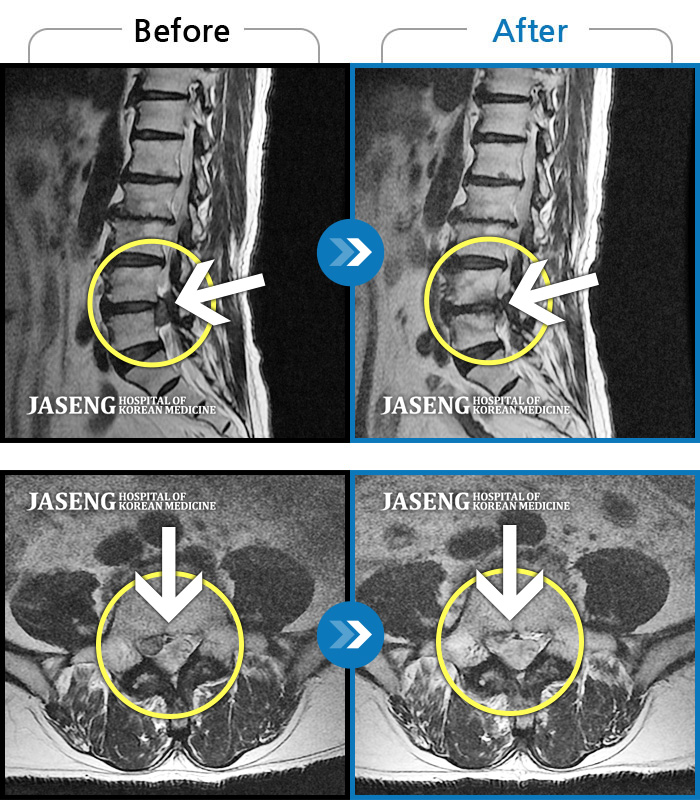

허리디스크

일산 · 김진수 원장

처음 내원 시 우측 엉덩이가 많이 아프고, 우측 다리로 근력 및 감각 저하도 있어 발목 움직임이 원활치 못했으며, 야간통으로 잠도 못 자고 통증 심하여 정상적인 활동이 힘든 상태셨습니다.

촬영시기

2023.12.04 ~ 2024.06.04

2024.06.21

조회수 565